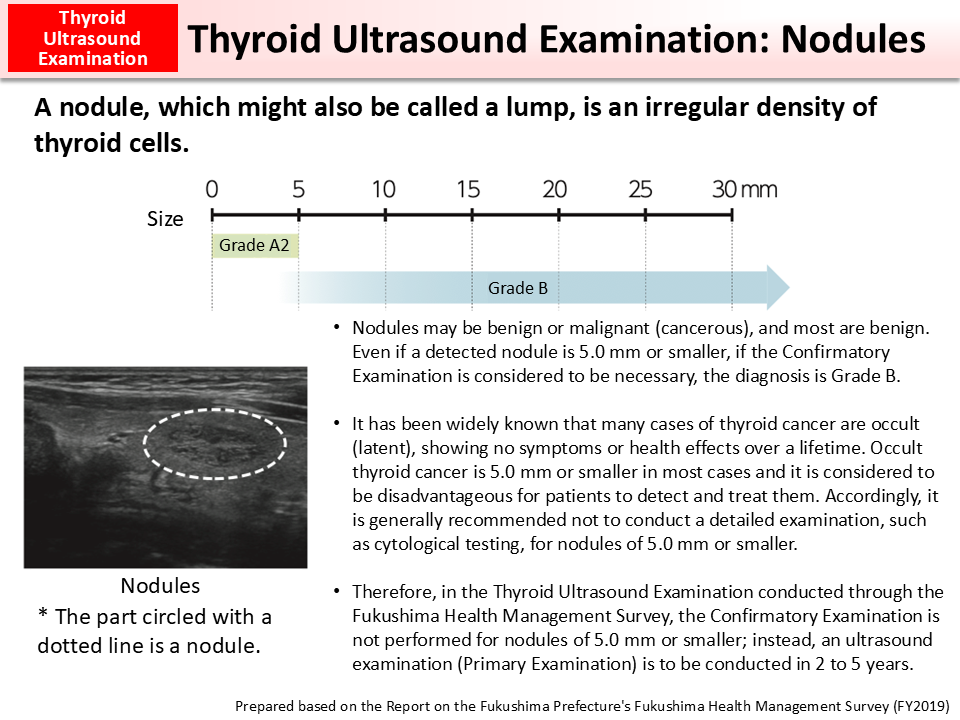

Thyroid Nodules

Thyroid Nodules

Thyroid Ultrasound

Thyroid Ultrasound